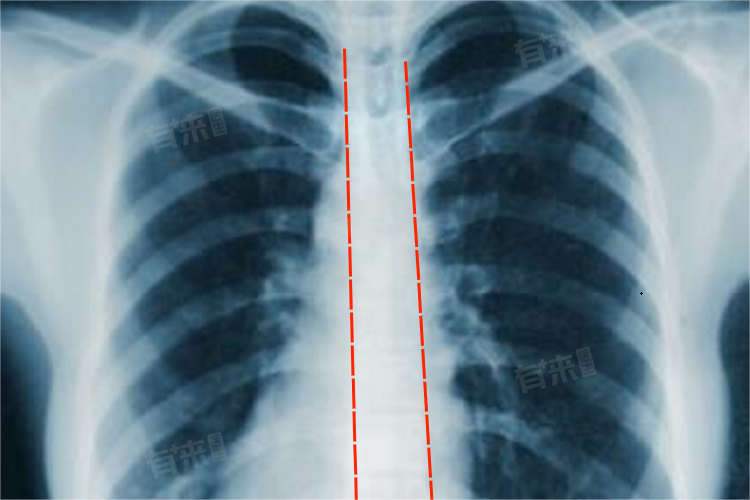

胸部正位检查是一种基础的影像学检查方法,通过X线对胸部进行前后方向的投射成像。患者需站立或仰卧于检查设备前,X线穿透胸部,不同组织对X线吸收程度不同,从而在成像板或探测器上形成黑白对比影像,用于观察胸廓、肺部、心脏大血管等胸部结构的形态及病变情况。

- 详细来说,胸部正位检查利用了X线的穿透性、荧光效应和感光效应。X线能穿透人体组织,由于骨骼、肌肉、脂肪、气体等组织密度不同,对X线吸收程度有差异。密度高的组织如骨骼吸收X线多,在影像上呈白色;含气的肺部组织密度低,吸收X线少,影像上显示为黑色;而软组织如心脏、大血管等则呈不同程度的灰色。

- 在心脏大血管方面,可大致评估心脏的大孝形态以及大血管的轮廓,辅助诊断先天性心脏并心脏扩大等疾玻而且该检查操作简便、价格相对低廉,是胸部疾病筛查和初步诊断的重要手段。

- 胸部正位检查虽有重要价值,但也存在一定局限性。例如,对于一些较小的病变,尤其是位于心脏后方、纵隔旁等隐蔽部位的病变,可能因重叠影像而漏诊。与胸部CT相比,胸部正位检查的分辨率较低,无法清晰显示肺部细微结构和病变内部特征。